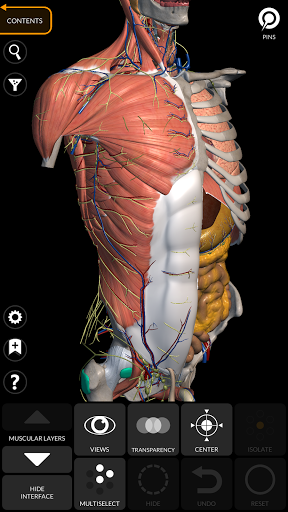

"Anatomy 3D Atlas" дозволяє легко та інтерактивно вивчати анатомію людини.

Завдяки простому та інтуїтивно зрозумілому інтерфейсу можна спостерігати кожну анатомічну структуру під будь-яким кутом.

Анатомічні 3D-моделі особливо деталізовані та мають текстури з роздільною здатністю до 4k.

АНАТОМІЧНІ 3D МОДЕЛІ

• Кістково-м’язова система

• Простий та інтуїтивно зрозумілий інтерфейс

• Обертайте та збільшуйте кожну модель Тривимірний простір

• Можливість приховування або ізоляції однієї чи кількох вибраних моделей

• Фільтр, щоб приховати або відобразити кожну систему

• Візуалізація м’язів через рівні шарів від поверхневих донизу до найглибших